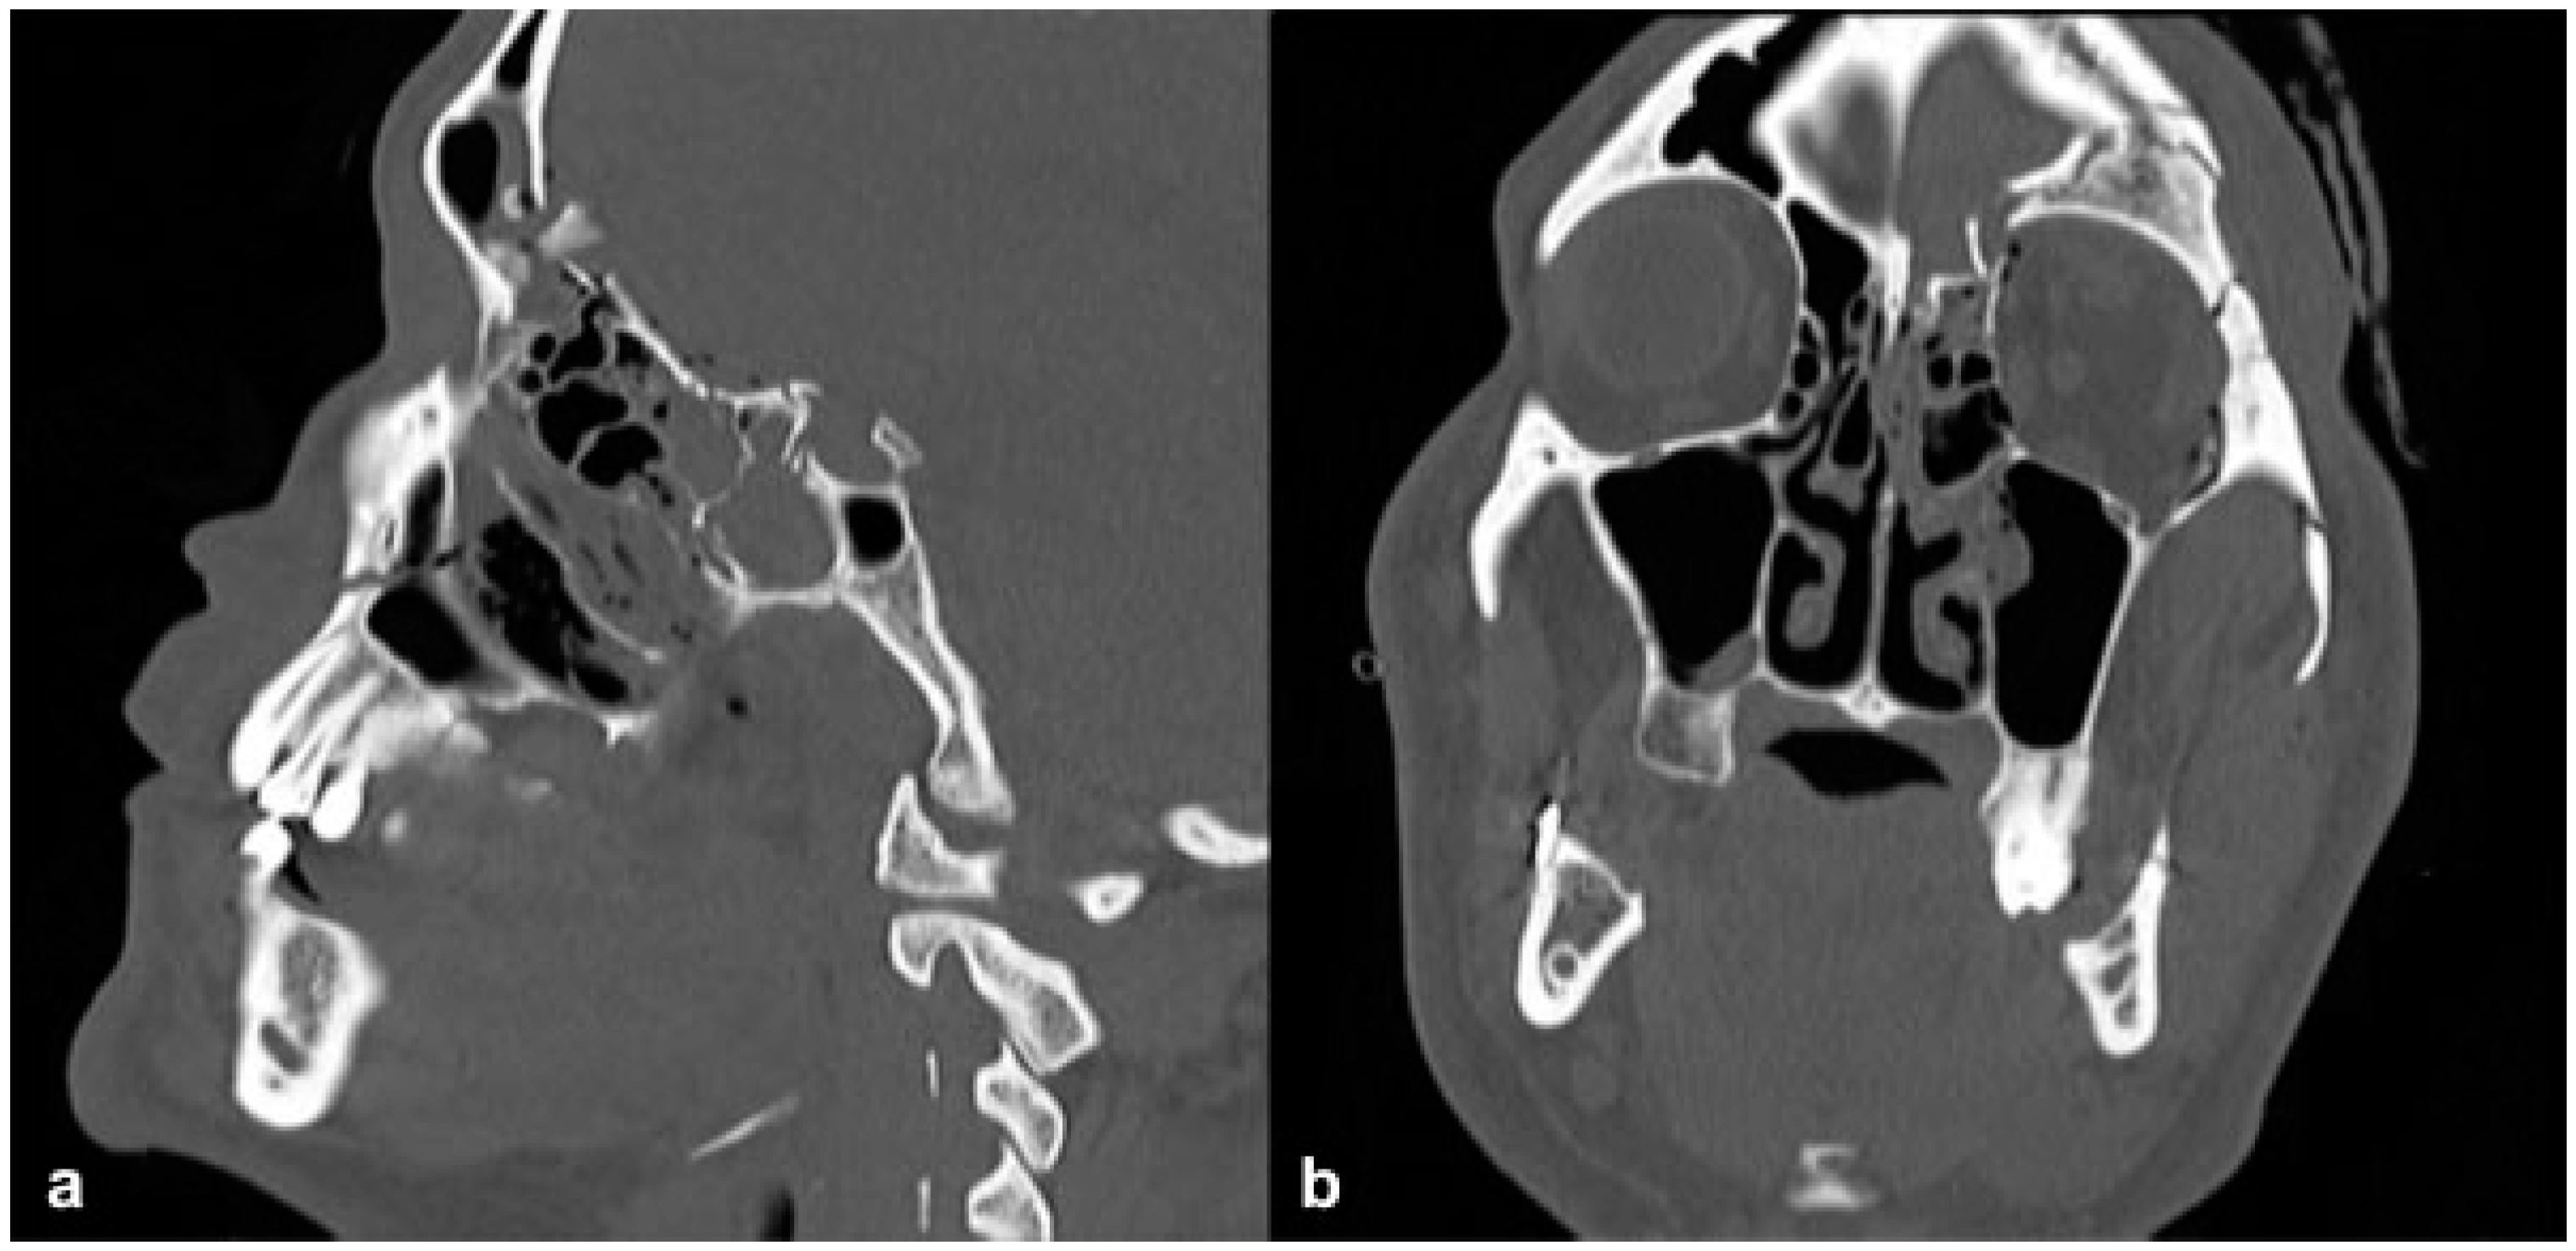

Fractures isolated to the posterior table are rarely observed (1–7%)[16,30,31] and are more common in younger patients. Typically, the posterior table is fractured in conjunction with injuries to the anterior table and FSOT (Figure 5). The sinus septae may transmit some of the anterior force to the posterior wall, or there may be direct posterior wall disruption.

Figure 5.

(a) CT in the sagittal plane demonstrating a displaced, comminuted fracture of the posterior table. There are also associated fractures of the anterior skull base along with obstruction of the FSOT with bony fragments. (b) CT in the coronal plane of the same fracture.